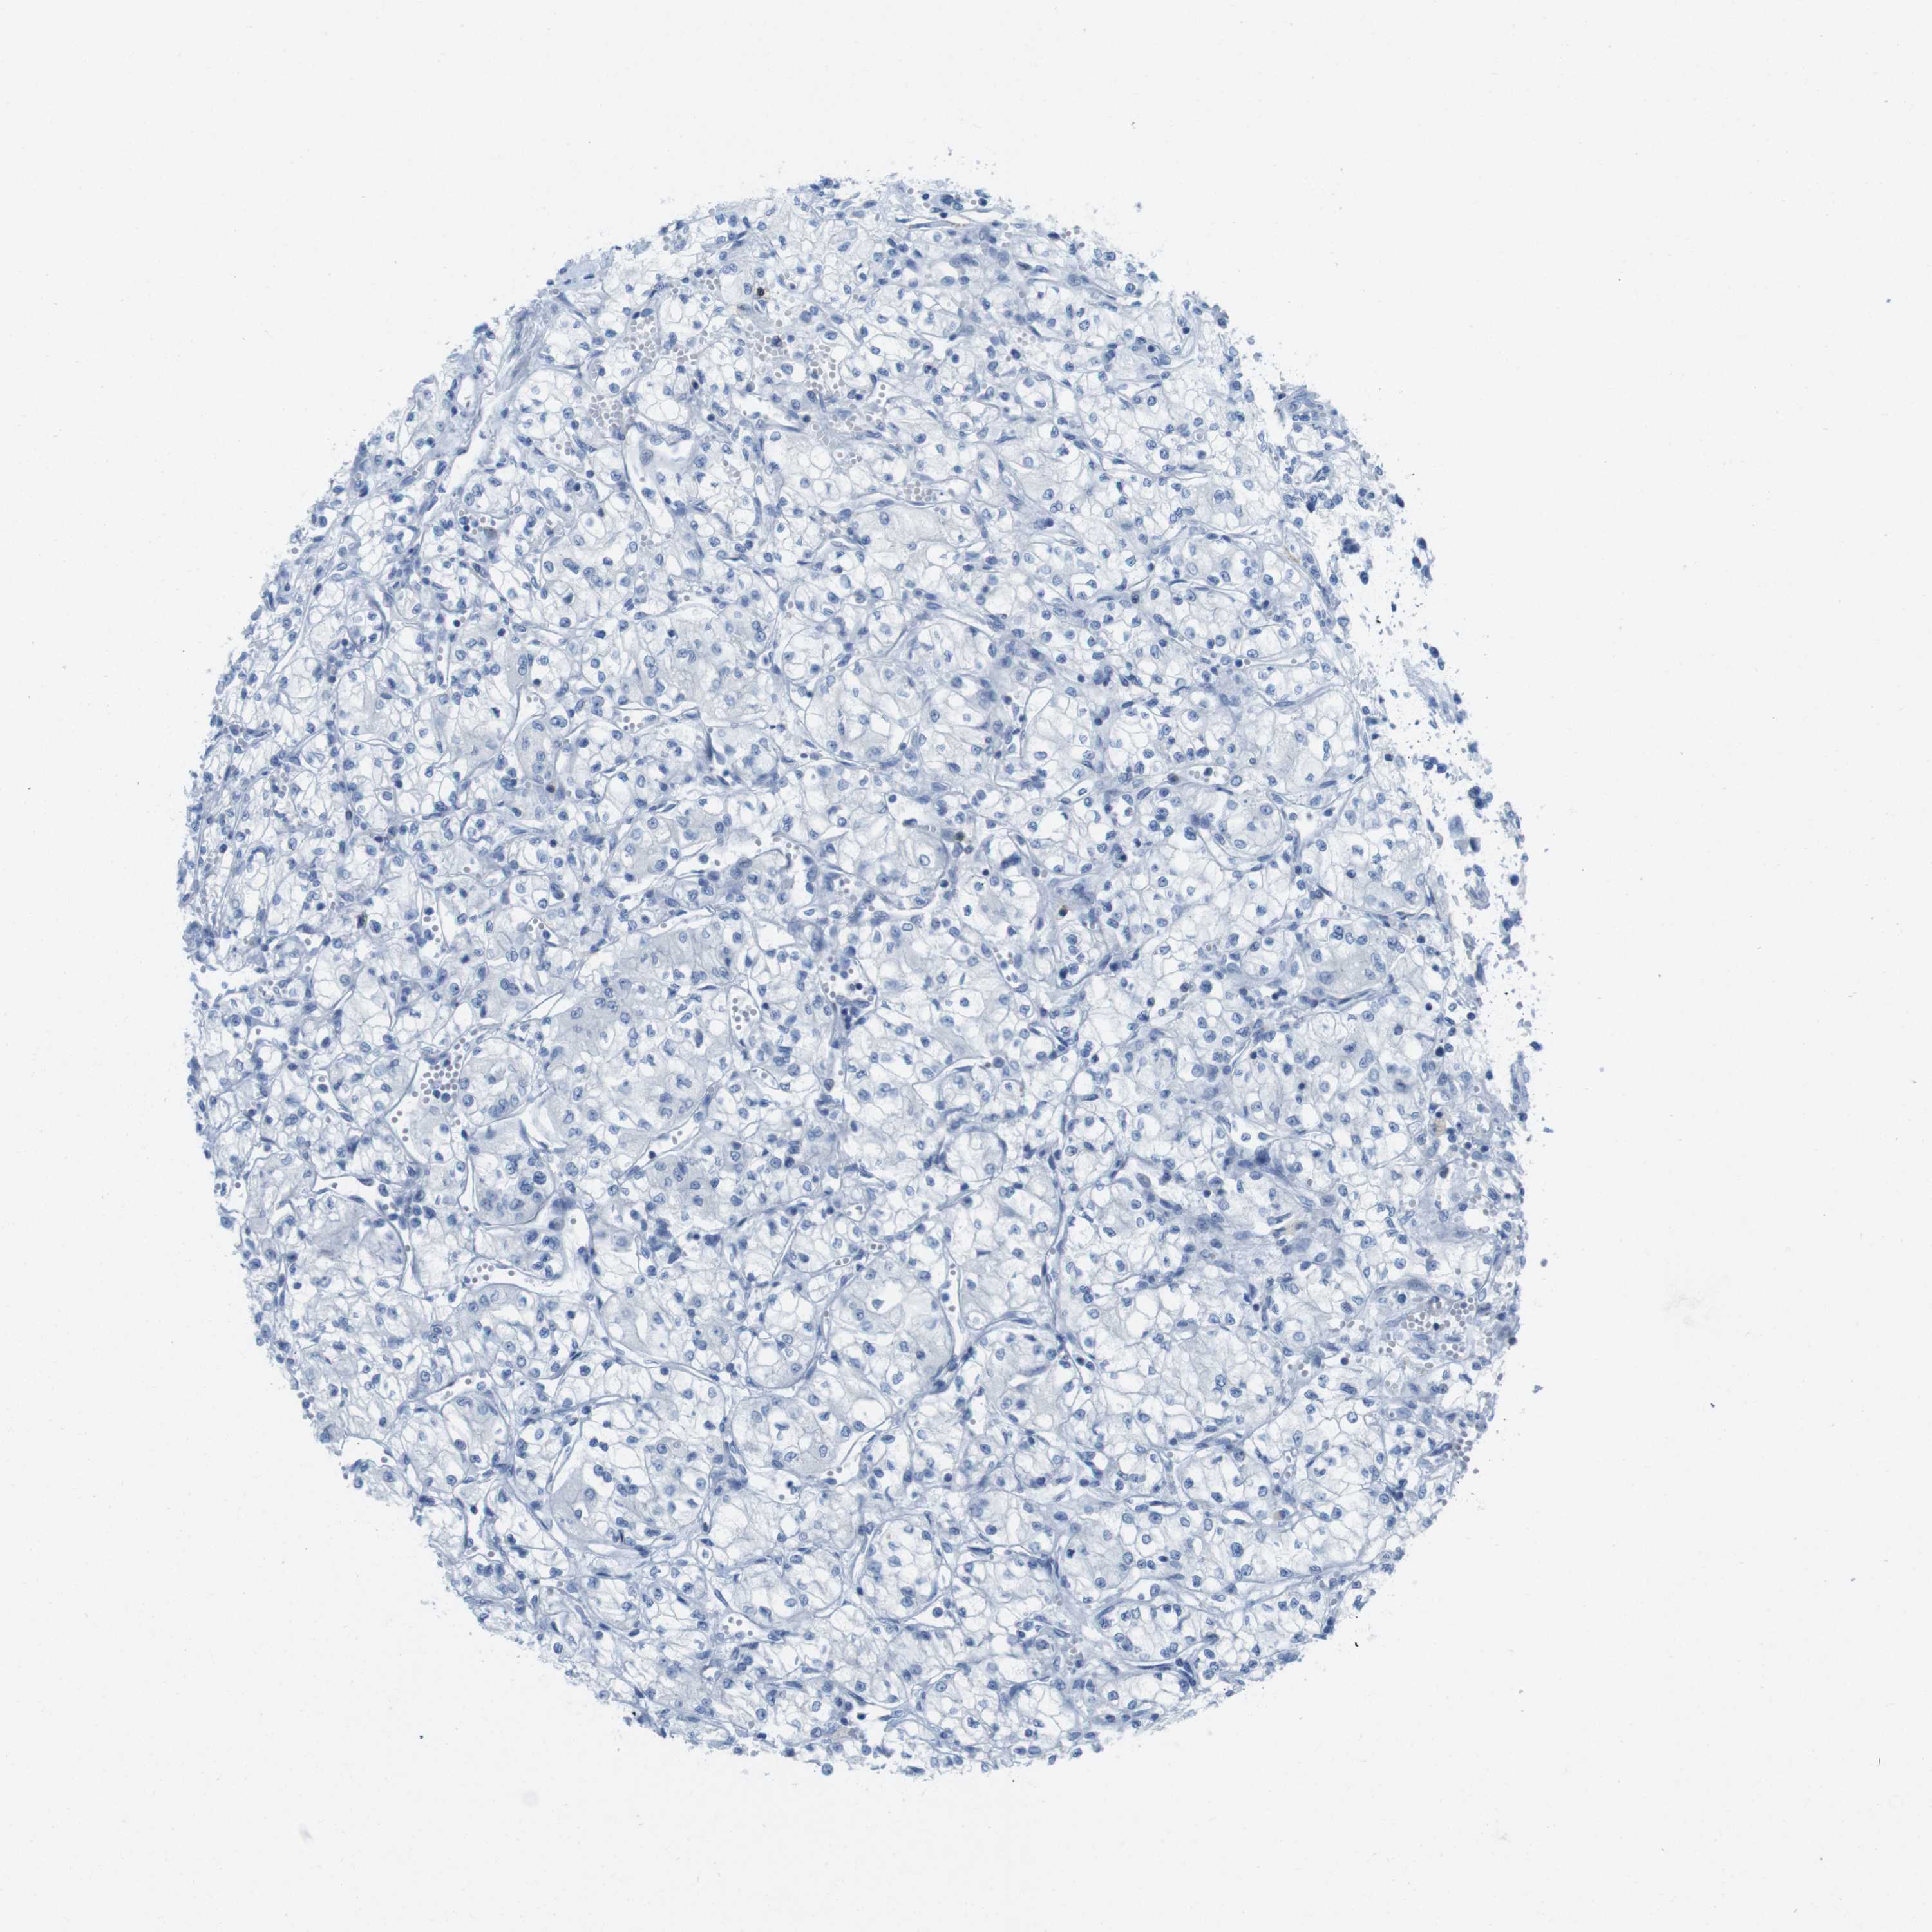

KIDNEY RENAL CLEAR CELL CARCINOMA (TCGA) - Interactive survival scatter ploti

The Survival Scatter plot shows the clinical status (i.e. dead or alive) for all individuals in the patient cohort, based on the same data that underlies the corresponding Kaplan-Meier plots. Patients that are alive at last time for follow-up are shown in blue and patients who have died during the study are shown in red.

The x-axis shows the expression levels (FPKM) of the investigated gene in the tumor tissue at the time of diagnosis. The y-axis shows the follow-up time after diagnosis (years). Both axes are complimented with kernel density curves demonstrating the data density over the axes. The top density plot shows the expression levels (FPKM) distribution among dead (red) and alive patients (blue). The right density plot shows the data density of the survived years of dead patients with high and low expression levels respectively, stratified using the cutoff indicated by the vertical dashed line through the Survival Scatter plot. This cutoff is automatically defined based on the FPKM cutoff that minimizes the p-score. The cutoff can be changed by dragging the vertical line or by entering a cutoff value in the square labeled "Current cut-off".

Under the Survival Scatter plot the p-score landscape (black curve; left axis) is shown together with dead median separation (red curve; right axis). Dead median separation is the difference in median mRNA expression between patients who have died with high and low expression, respectively. It is calculated as follows: median FPKM expression of dead patients with high expression - median FPKM expression of dead patients with low expression. This is intended to aid the user in visually exploring custom cutoffs and the associated p-scores and dead median separation.

Individual patient data is displayed and can be filtered by clicking on one or more of the category buttons on the top of the page. Categories describing expression level and patient information include: high, low, alive, dead, female, male and tumor stages. The scale of the x-axis can be toggled between linear and log-scale by clicking on the "x log" button. Mouse-over function shows TCGA ID, patient information and mRNA expression (FPKM) for each patient.

& Survival analysisi

Kaplan-Meier plots summarize results from analysis of correlation between mRNA expression level and patient survival. Patients were divided based on level of expression into one of the two groups "low" (under cut off) or "high" (over cut off). X-axis shows time for survival (years) and y-axis shows the probability of survival, where 1.0 corresponds to 100 percent.

CD5 is not prognostic in Kidney Renal Clear Cell Carcinoma (TCGA)

: 4.15

Average pTPM 4.0

Number of samples 521